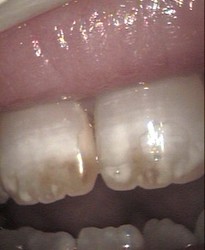

Brown spots on permanent front teeth micro abrasion

direct composite veneers